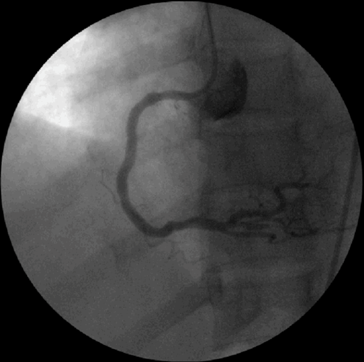

Kết quả chụp động mạch vành: động mạch vành phải tắc hoàn toàn, động mạch liên thất trước hẹp 50%, động mạch mũ hẹp 50%.

Bệnh nhân được đặt stent cấp cứu với thời gian cửa-dây dẫn trong vòng 30 phút với kích thước 4.0 x 28mm, kiểm tra động mạch thông tốt, dòng chảy TIMI3: